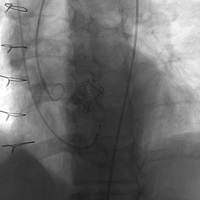

病例三(经心尖二尖瓣瓣中瓣)

患者女性,78岁,既往行二尖瓣生物瓣置换术,置入HANCOCK II 27#瓣膜一枚。STS评分26.93 %,属于外科换瓣手术极高风险患者。术前心脏超声示原二尖瓣生物瓣衰败,瓣叶明显增厚、变形,关闭极差,可及大量反流。术前充分评估,经心尖途径植入25# Renato球扩式瓣中瓣,释放成功后瓣膜功能良好,无明显瓣中及瓣周反流,平均跨瓣压差2.6mmHg。

术前左室造影 术后左室造影